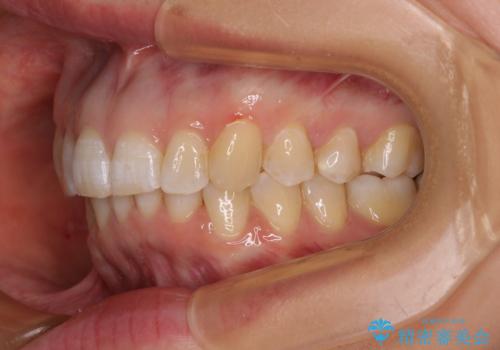

- 上顎前歯の前方に傾斜した咬み合わせを気にして来院された患者様です。

奥歯の咬み合わせを見ると、上顎が下顎に対して相対的に前方にありました。

深い咬み合わせを改善するためには、上顎臼歯を後方に移動させつつ、下顎の小臼歯を直立させる必要があります。

インビザライン単体で対応ることも検討できますが、達成する可能性が低いため、カリエールディスタライザーという補助装置を併用して、より確実性を上げることとしました。

奥歯の咬み合わせと深い咬み合わせを改善した後、インビザラインで歯列を整えることとしました。